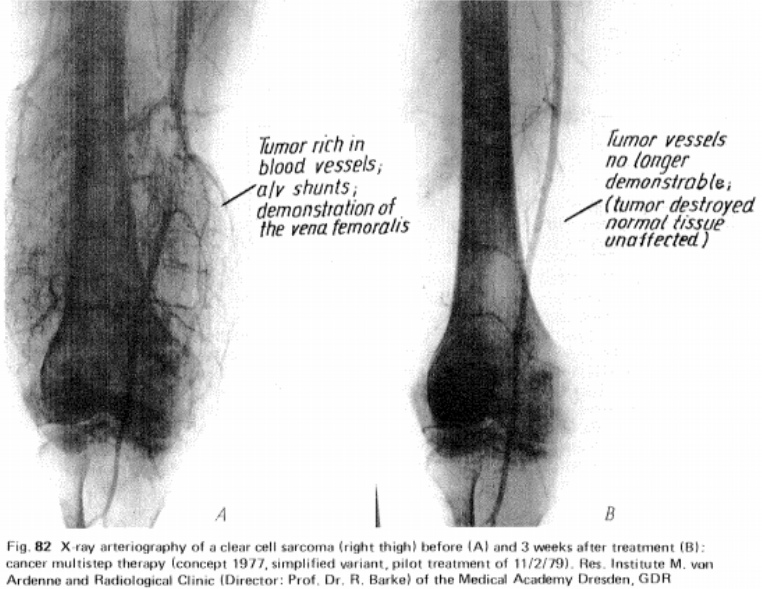

If you are a health care practitioner or researcher, you might be inclined to investigate what Manfred von Ardenne's textbook methodologies might be able to do in a clinical environment that go beyond the sports and life performance aspects we've discussed. Click the image for context.

To expand on this idea in a parallel direction, read the study abstract.

We will leave this without comment save one: The Velocity O2 Training as outlined here is designed as a toolset for exercise physiology in order to to enhance life performance and has NOT been designed with any capability nor is it intended to diagnose, treat, cure or prevent any disease or medical condition. The FDA has not evaluated any statement herein nor this methodology for any such intended purpose.